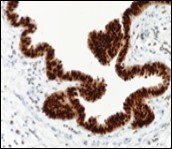

Alternatively, cutaneous ciliated cyst can be lined by non ciliated cuboidal or columnar epithelium with intermingled intercalated, dark or round peg cells. Foci of squamous metaplasia can be occasionally exemplified in the adherent epithelium whereas mucinous cells or apocrine-like features are exceptional 6, 8. Figure 1, Figure 2, Figure 3, Figure 4, Figure 5, Figure 6, Figure 7, Figure 8, Figure 9, Figure 10, Figure 11, Figure 12. 11, 12, 13, 14, 15, 16, 17, 18, 19.

Figure 11.Cutaneous ciliated cyst with immune reactivity to cyto-keratin (19).

Epithelium of cutaneous ciliated cyst is immune reactive for pan cytokeratin (CKae1/ae3) antigens, epithelial membrane antigen (EMA), oestrogen receptors (ER), progesterone receptors (PR), Wilm’s tumour protein (WT-1) and paired box gene 8 (PAX8). Immune non reactivity is cogitated for S100, smooth muscle actin (SMA), carcino-embryonic antigen (CEA), desmin, thyroid transcription factor(TTF1), p63 and glial fibrillary acidic protein (GFAP).

Smooth muscle actin (SMA) is immune non reactive, thereby suggesting an absence of smooth muscle within the cyst wall. Intense immune reactivity can be cogitated within epithelial nuclei for oestrogen receptors (ER) and progesterone receptors (PR). Aforesaid immune reactions are indicative of Mullerian origin of cutaneous ciliated cyst.

Focal epithelial staining for periodic acid Schiff’s(PAS) stain is enunciated 4, 5. Pan cytokeratin (CKae1/ae3) are diffusely immune reactive.